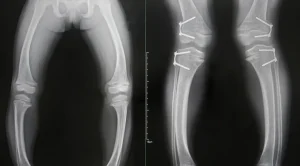

3. Röntgen

Kemik deformasyonlarını tespit etmek için röntgen filmi çekilebilir. Röntgen, kemiklerin zayıflamasını ve deformasyonunu net bir şekilde gösterebilir.

1. Kemik Deformasyonları

Raşitizm, kemiklerin normal şekilde sertleşmemesine ve büyümesine yol açar. Bu durum, uzun kemiklerde (bacaklar, kollarda) deformasyonlara neden olabilir. Bacaklar genellikle eğilebilir ve dizler birbirine yakınlaşabilir. Ayrıca, omurga eğriliği (skolyoz veya kifoz) gelişebilir.

Şiddetli kemik deformasyonları durumunda fiziksel terapi önerilebilir. Ayrıca, çok ileri seviyedeki deformasyonlar cerrahi müdahale gerektirebilir.